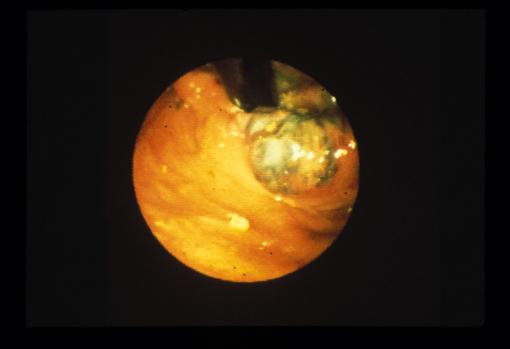

Rectal malignant melanoma with regional lymph node metastasis demonstrated by a double contrast barium enema.

[ Image ID:5910 ]

Malignant melanoma/

Large intestine(Colon)/Rectum

Endoscopy

40 -

muscularis propria